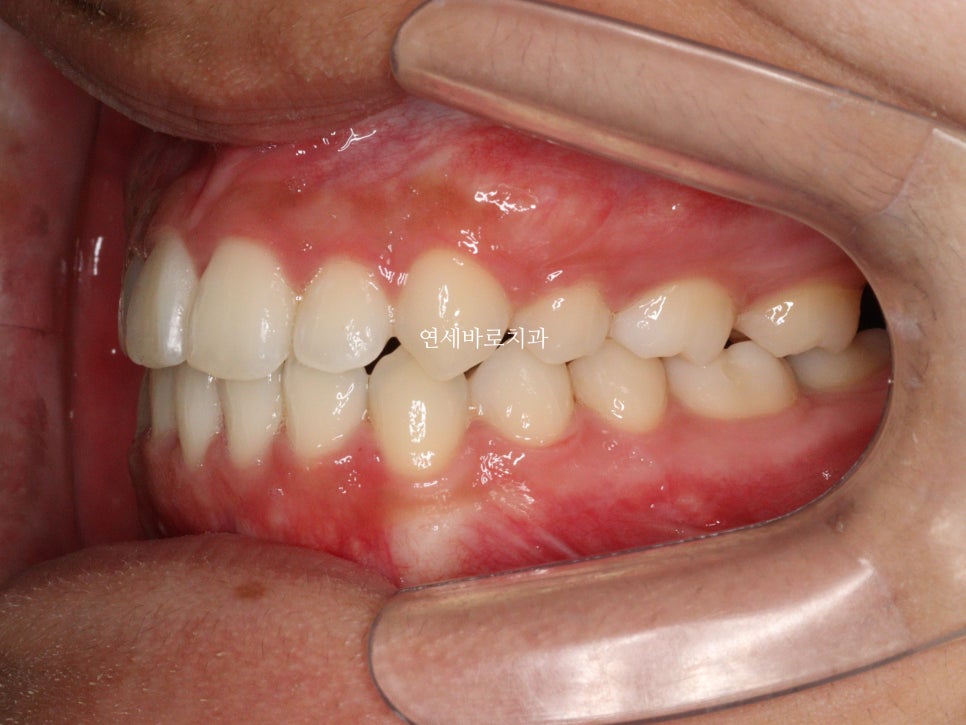

최근에 오셨을때 모습입니다.

아쉽게도 처음 끝날때와는 약간은 다른 중심선을 관찰하였습니다.

하지만 좌우 교합은 긴밀하게 유지되고 있었고 안모의 변화 등 다른 부작용은 관찰되지 않았습니다.